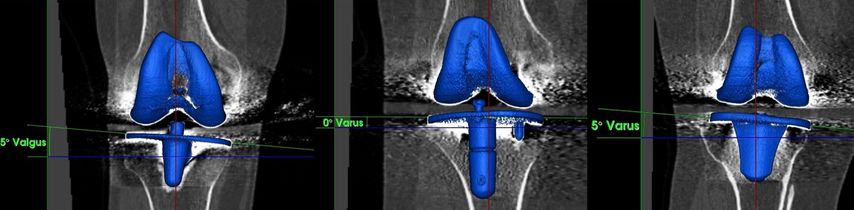

Abb. 3: Koronales Alignment der Femurkomponente nach konventioneller TKE, gemessen an 3D-rekonstruierten CT-Aufnahmen mit einer handelsüblichen Software.30 Das Ziel war bei allen Patienten ein MA mit einer neutralen Beinachse